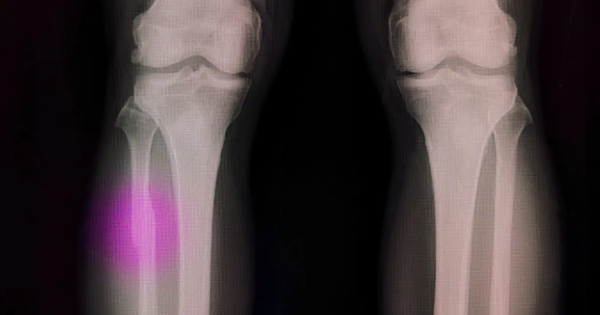

Nghiên cứu đặt mục tiêu xác định tỷ lệ các tổn thương ở bề mặt nhãn cầu (khô mắt, canxi hóa kết - giác mạc) và đục thể thủy tinh ở bệnh nhân chờ ghép thận; phân tích mối liên quan giữa các biểu hiện tại mắt với tình trạng toàn thân trước ghép.

Kết quả cho thấy tình trạng khô mắt phổ biến (64% bất thường), rối loạn phim nước mắt mức nhẹ - vừa chiếm đa số. Các yếu tố gây tổn thương bề mặt nhãn cầu của bệnh nhân trước khi mổ ghép thận có thể là tuổi cao, thời gian mắc bệnh/điều trị kéo dài, tăng ure/creatinin và phương thức điều trị thay thế thận.